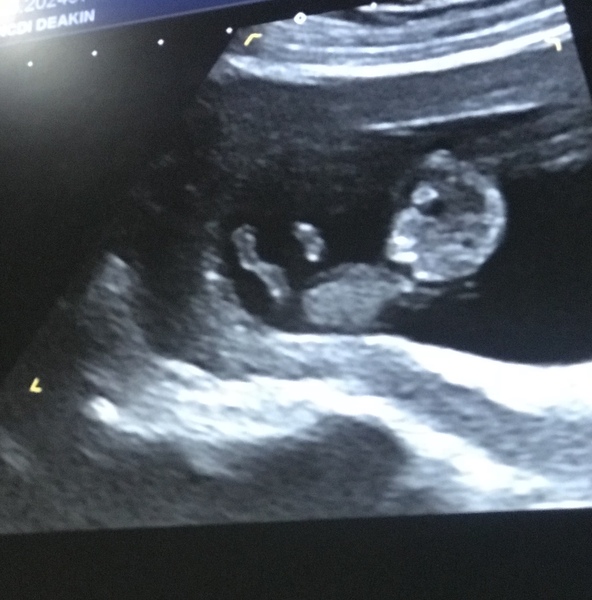

Finally had my dating scan today, turns out I’m 9wks and 6days so that’s handy to know. Little poppet looks good and was annoyingly active which made getting a good shot tricky but it’s definitely a baby lol I sent the pic to DH and just got “evil seedling” in response (he’s joking.. the evil seedling is surely his jet pack fuelled sperm!!)